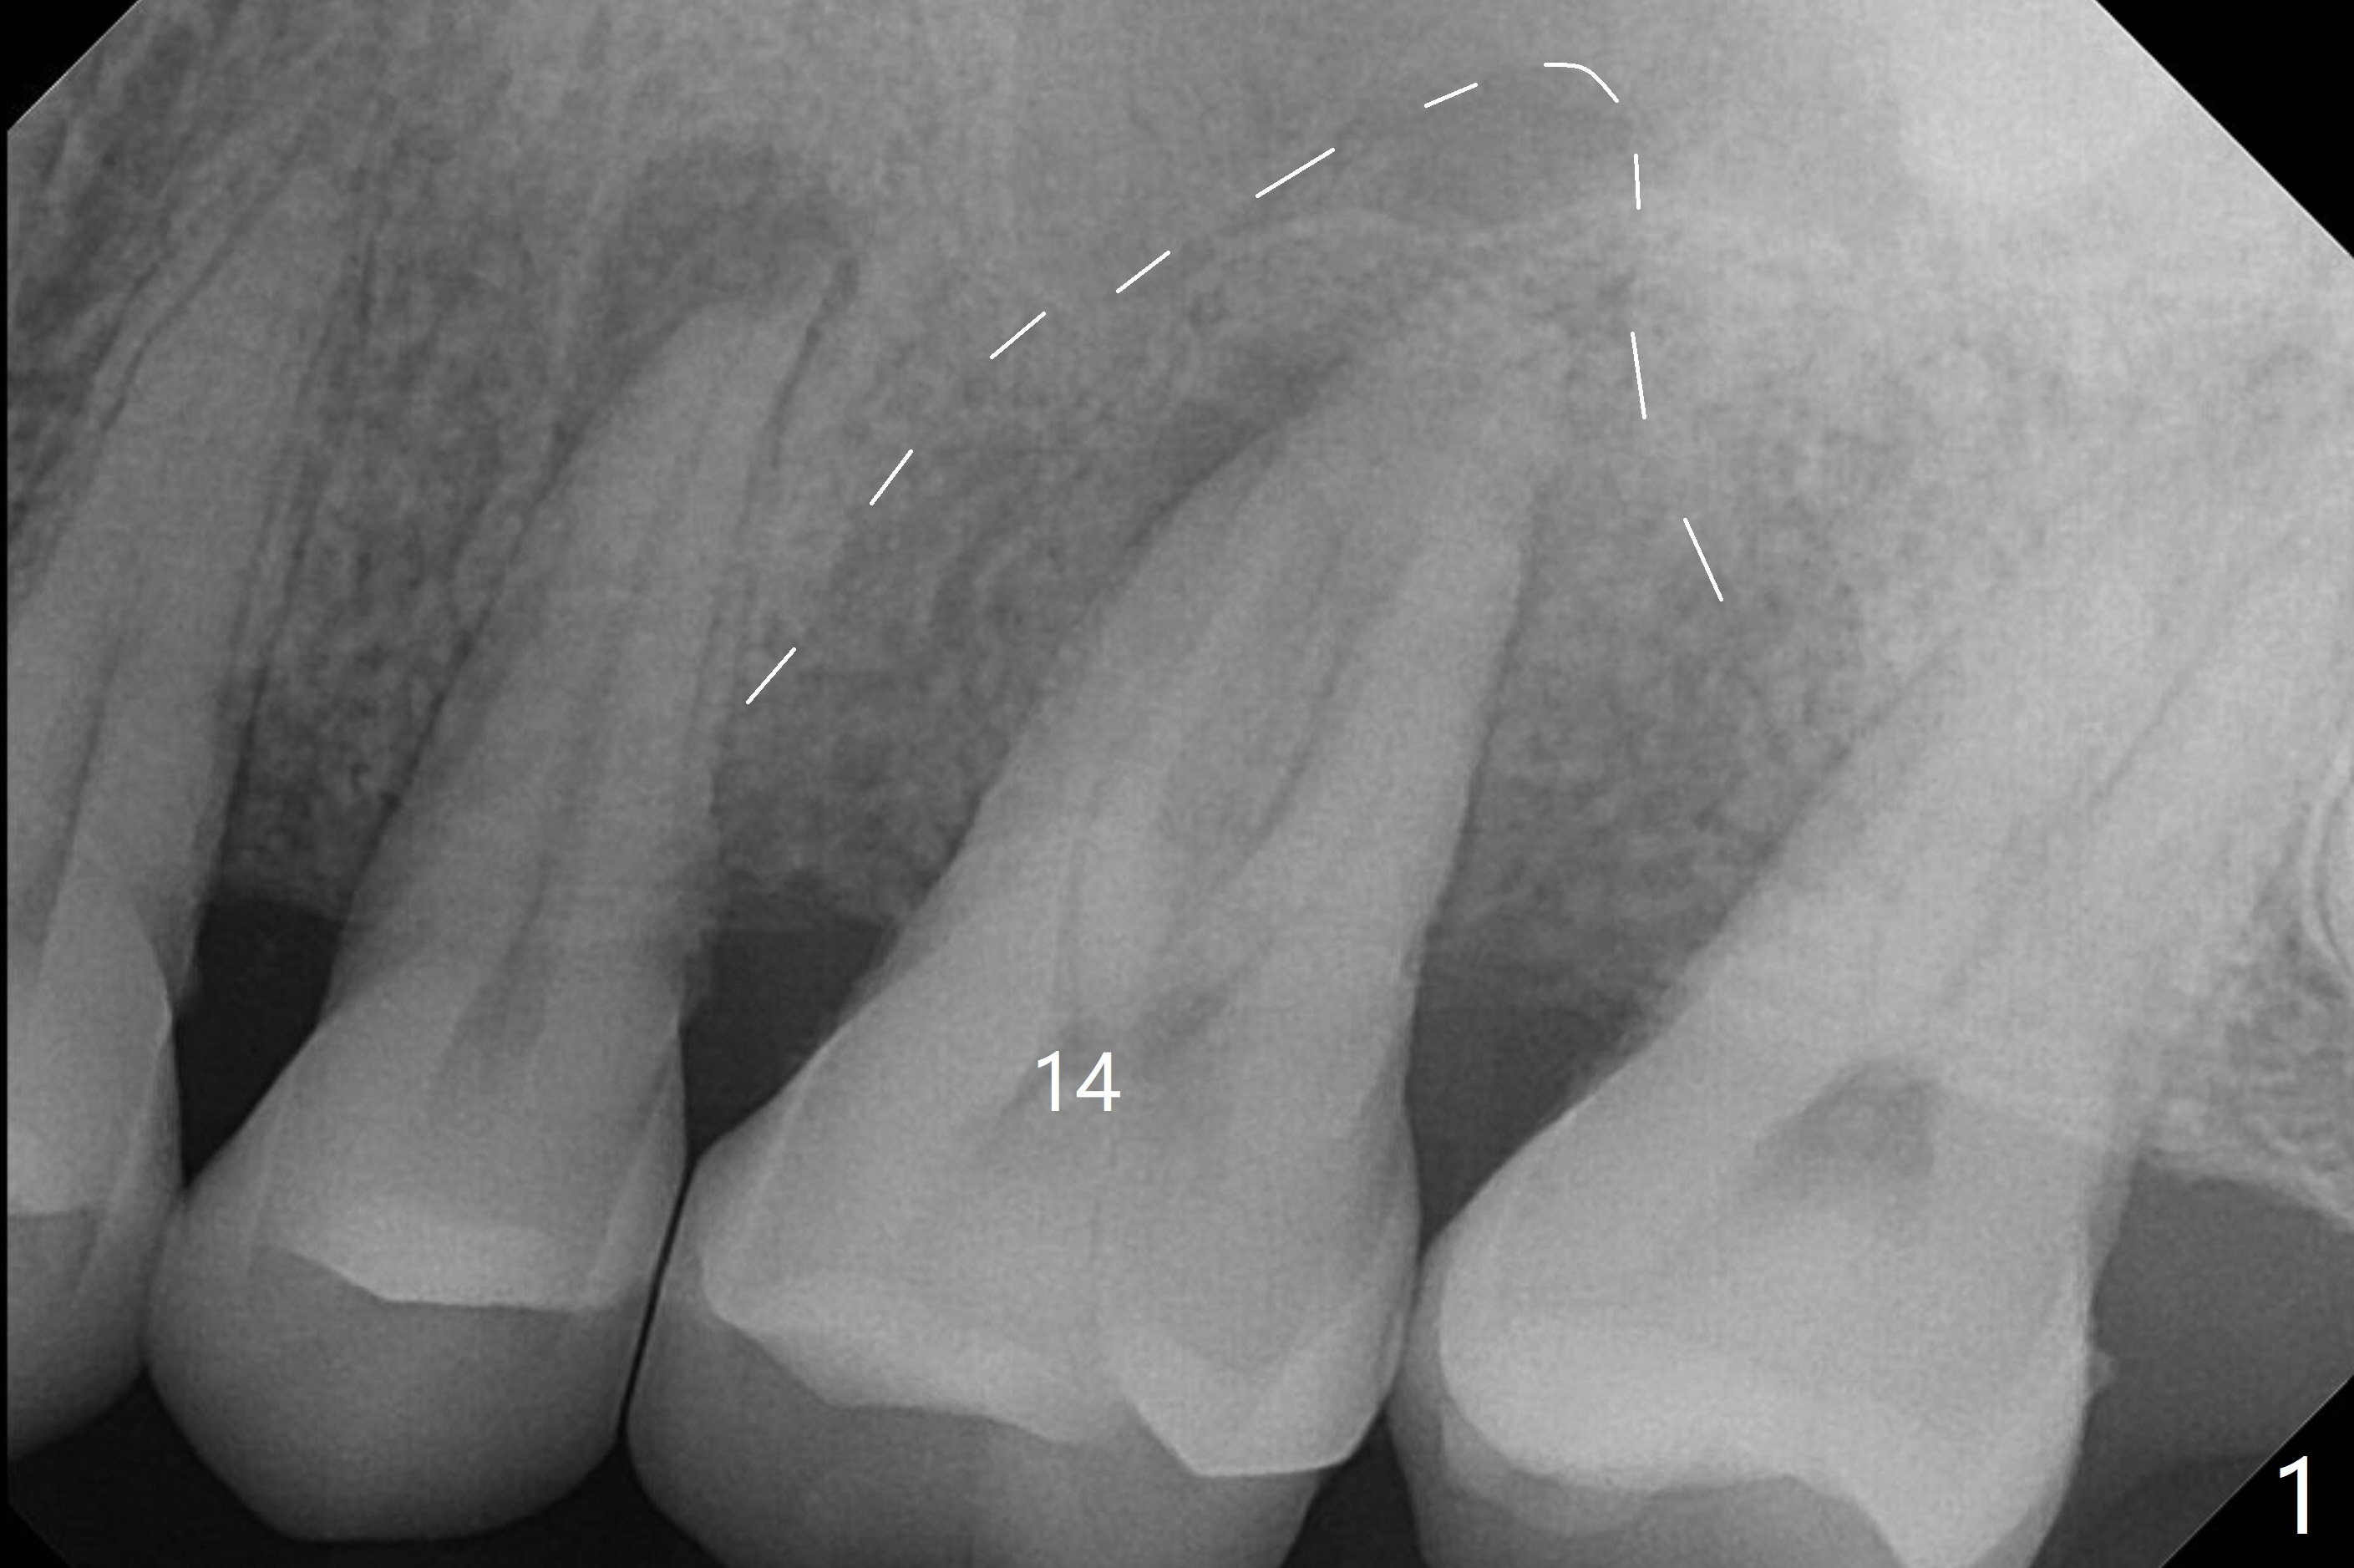

A 45-year-old man has chronic generalized moderate localized severe periodontitis; gingival recession is severe lingual of the tooth #14 with mobility II (Fig.1). The low bone density outline (Fig.1 white dashed line) is larger than the roots, suggesting lingual bone loss/low lingual crest. Although the bone height seems to be 11 mm (Fig.2), the bone responsible for primary stability of an implant will be apical (Fig.3 *,4). The implant platform will be ~3 mm subcrestal buccal, while ~3 mm supragingival lingual (Fig.5). The diameter of the implant will not be too large, 4.5 mm (dummy). There will be not biologic width issue. The large perimplant gap will be closed with sticky bone. Severe palatal gingival recession is shown pre- (Fig.6) and post- (Fig.7) SRP. #30 Gutta Percha inserted palatal reaches the highest point of the low bone density lesion (Fig.8). Pulpal test and CT will determine that endodontic treatment can regrow bone or that socket preservation is needed with Cytoplast.